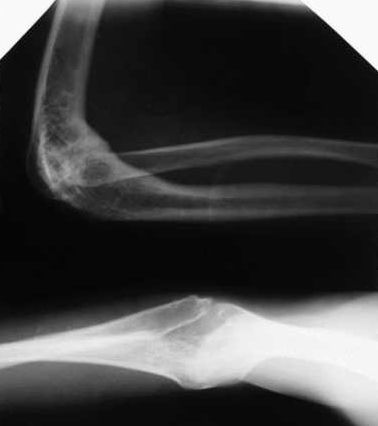

Обратился пациент 13 лет с анкилозом левого локтевого сустава, после остеомиелита.

Несколько лет тому назад больному пытались сохранить сустав в одой

клинике. Из документов известно, что резецировали головку лучевой

кости и сформировали блок плечевой кости.

На сегодняшний день: локтевой сустав в положении сгибания 80гр.

просупинационные движения 10/0/10. Пациент не может самостоятельно надеть ботинки и

застегнуть брюки .